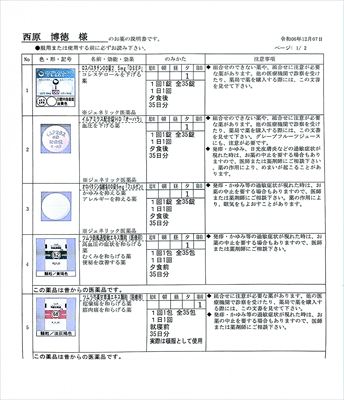

2024.12.7 西原クリニック定番薬 (リンデロンはベタメタゾンに変更:同等)